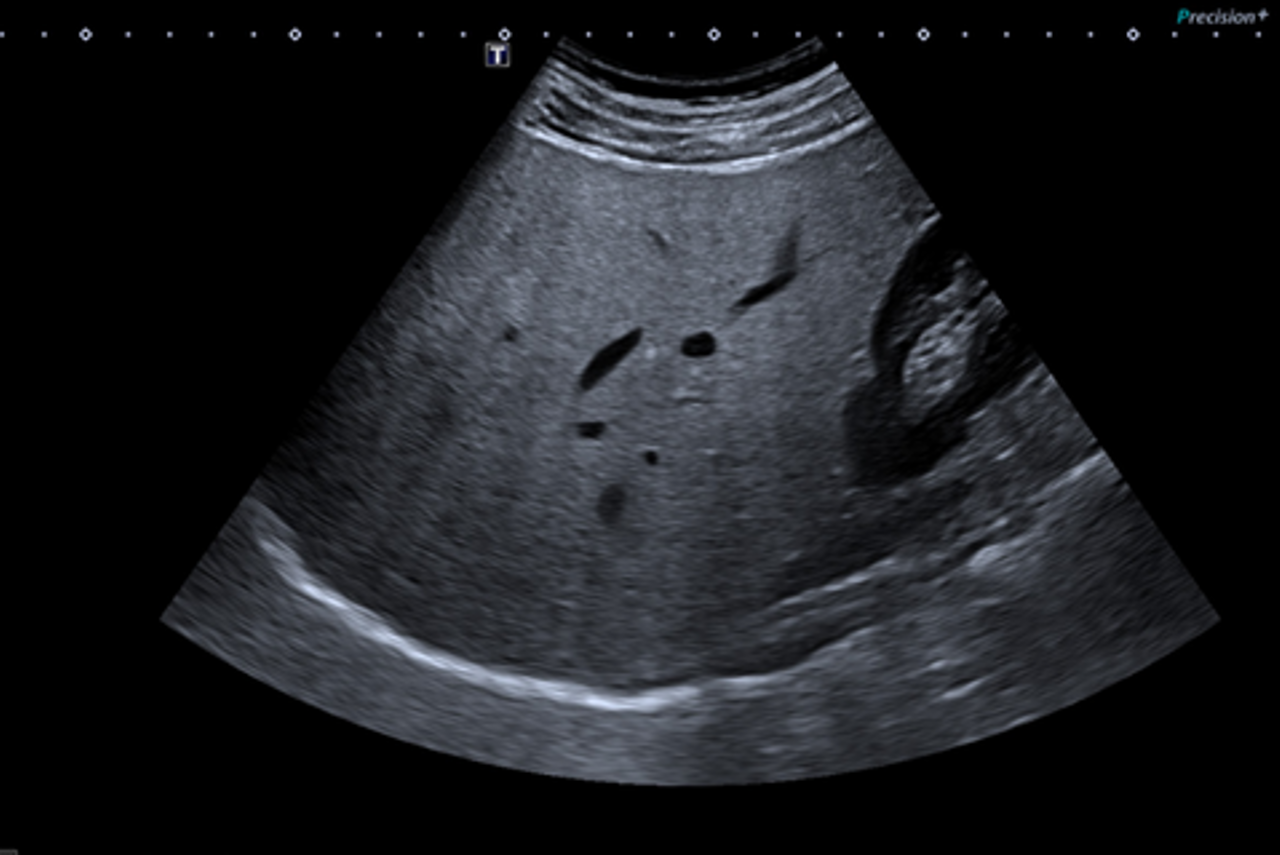

A Liver Health Assessment combines ultrasound imaging with two non-invasive technologies:

- Liver elastography measures liver stiffness

- Fat quantification measures the amount of fat in the liver

Together, these provide a valuable assessment of liver health.

The scan – The sonographer will gently move the probe over the right side of your abdomen, between the ribs. You may be asked to change position or hold your breath for short periods.